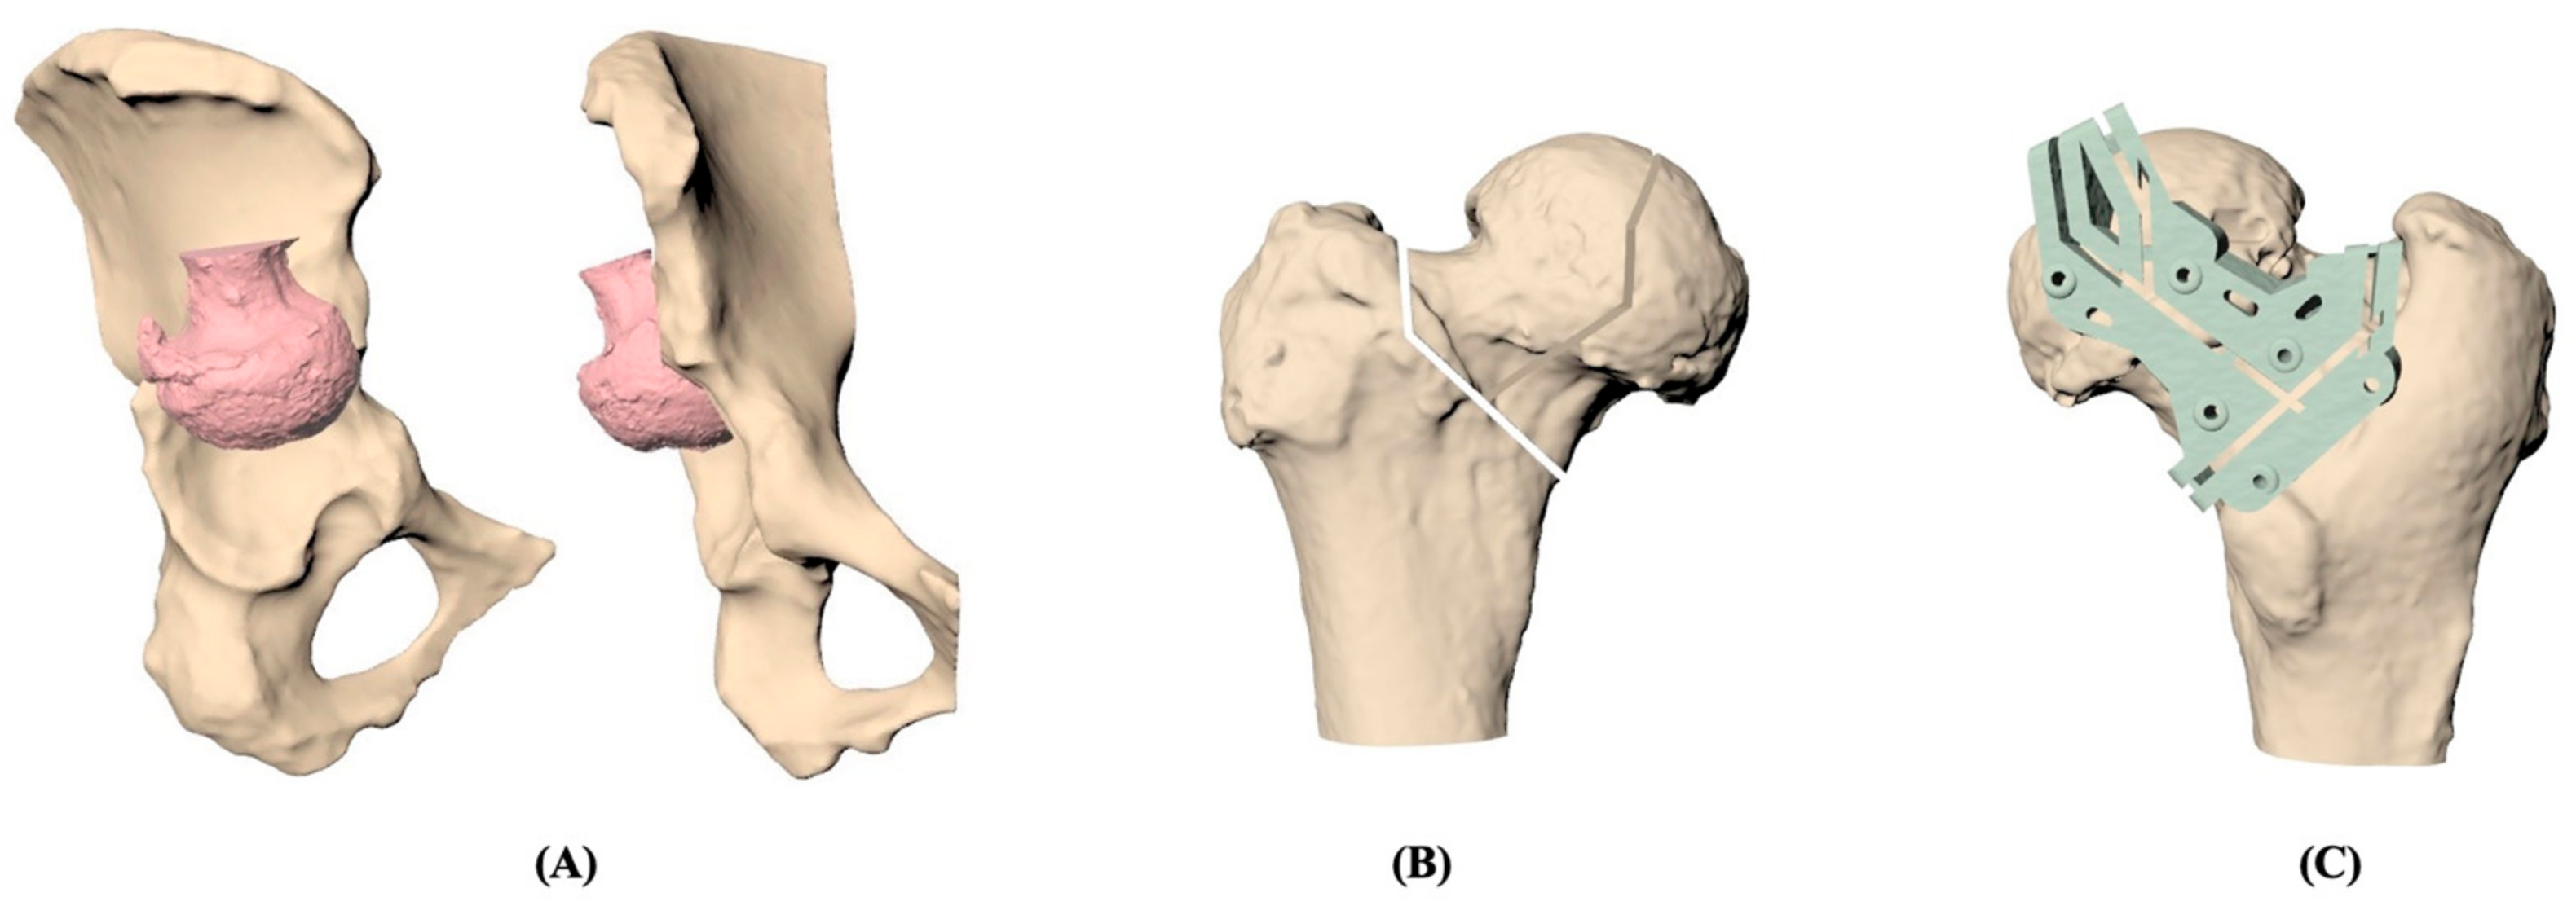

Based on individual CT images, the 3D models of the pelvis and femur were reconstructed and demonstrated in Figure 1. The femoral head and neck were resected under simulation and repositioned at the acetabulum according to the surgeon’s guide. Once the position of the resected femoral head was determined, the osteotomy could be designed for the best fit between the contact surfaces of the acetabular and osteotomized femoral head. The patient-specific cutting jig was designed to fit the patient’s proximal femur with six pin holes for stable fixation and was composed of the guiding slots that were generated in line with the osteotomy. The jig was then manufactured by a commercial 3D printer with medical-grade nylon. Before clinical use, moist heat sterilization was implemented to ensure that no visible deformation happens on the cutting jig.

Figure 1.

The 3D model reconstruction process of total hip arthroplasty using patient-specific instrumentation (PSI). (A) Preoperative reconstruction of pelvis and femur. (B) Determination of the position of osteotomy in the femoral head. (C) Simulation of the 3D-printed patient-specific cutting jig on the femoral head.